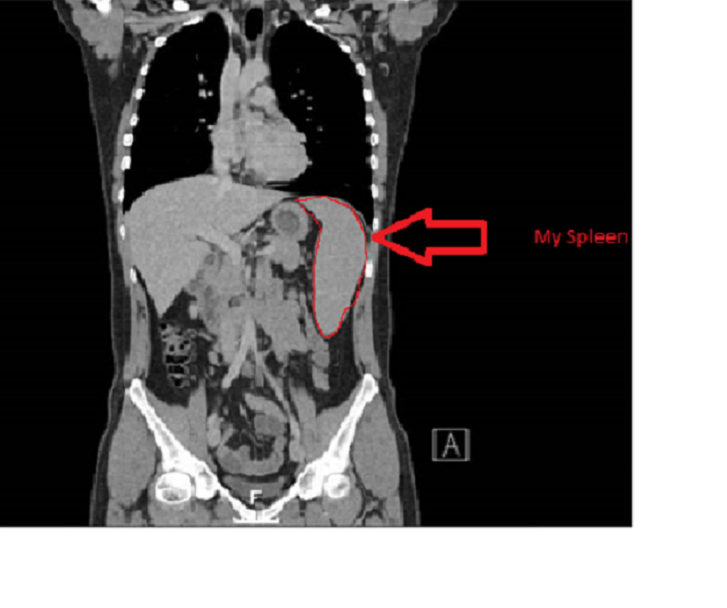

Its a very strange experience seeing your own insides. The Professor showed this to me in a video, the pulsing of my heart and the pumping of my blood. I only have a couple of snap shots to share but yes that is me, at a visceral level. I think we often forget we are all composed of organs, fleshy bits and blood but this brings it home to you. We obviously have consciousness, a mind to think with, an appreciation of art and the abstract but on a very basic level we are just an organic machine. Its important to remember this as machines sometimes go wrong and there often isn’t a reason why. Its not because I inhaled asbestos or ate bad food or bungee jumped, something just went wrong, it just did. Its like your gearbox failing or your clutch slipping. I’m just lucky that what went wrong didn’t write off my machine. These photos are very odd to look at. Welcome to the sum total of my body.

Anyway, I have highlighted my spleen on the picture. I recognise a few of the other organs, feel free to take the picture and mark what they are on there. If anyone does I’ll blog that too.